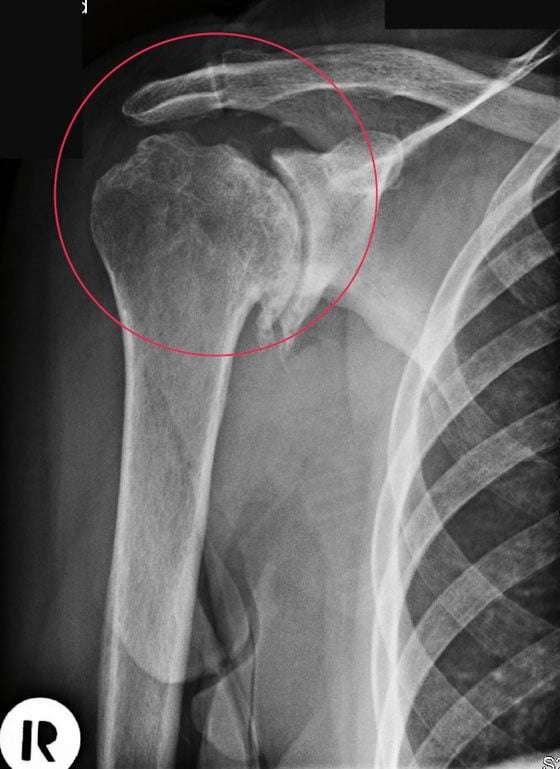

Артрозо-артрит плечевого сустава

Этот сустав образован головкой плечевой кости и суставной впадиной лопатки. Заболеванием поражается хрящевая губа, расположенная по краям суставной впадины. Она уже не смягчает толчки и сотрясения при движении костной головки.

У человека возникают дискомфортные ощущения при отведении плеча назад, подъеме руки вверх. Во время рецидивов он намеренно ограничивает движения, чтобы не испытывать острые боли.

Разница в рентгенологических картинах:

- при артрозе плотность костной ткани повышается (остеосклероз), по краям суставных площадок образуются наросты-остеофиты, на фоне остеосклероза возможны единичные кистоподобные полости, окруженные склерозированным ободком;

- при артрите плотность кости уменьшается (остеопороз), формируются краевые дефекты костной ткани и множественные кисты.